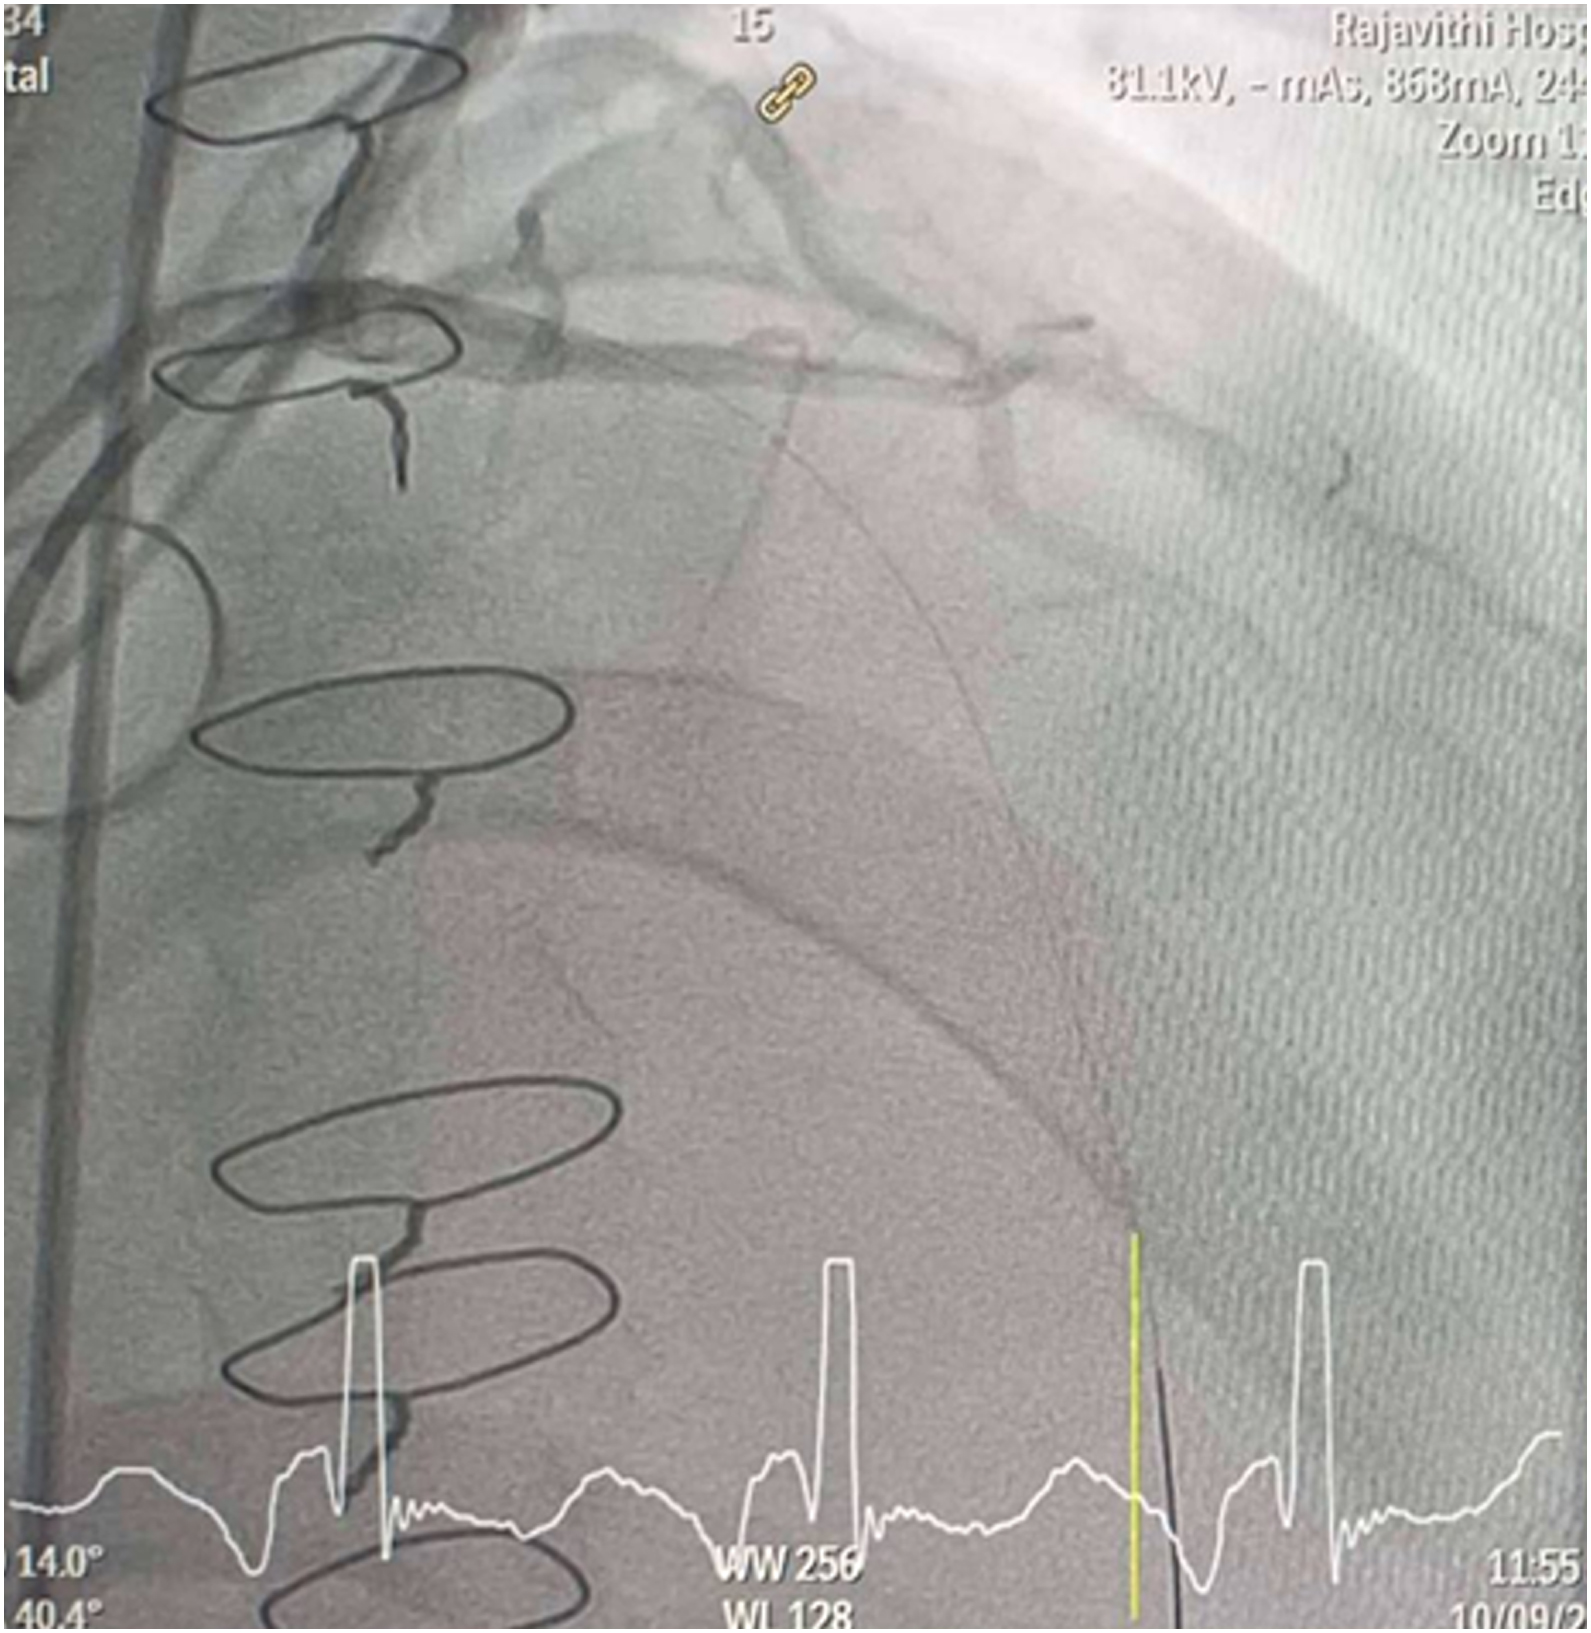

CAG was performed with right femoral approach with JL 4.0/7 Fr, JR 4.0/6 Fr diagnostic catheter showed

Right dominant

LM : mild irregular, non significant stenosis.

LAD : total occlusion mLAD.

LCx : mild irregular, non significant stenosis.

RCA : non significant stenosis.

Inserted Sion wire and thrombuster to LAD revealed multiple red clots.SC balloon 2.0 x 15 mm, then 2.5 x 15 mm, was inflated at mLAD up to 12 atm. IVUS insertion to LAD revealed vessels¡¯ size LM 5-5.5 mm, pLAD 4-4.5 mm, mLAD 3-3.5 mm with intraluminal thrombus, dLAD 2.75-3 mm. Multiple inflations were done at mLAD with SC balloon 2.5 x 15 mm. After multiple SC balloon inflations, the CAG revealed slow flow phenomenon. Then, the operator performed thrombus aspiration, multiple SC balloon 2.0 x 15 mm inflation and gave IC integrillin 3.4 ml. The final angiogram was acceptable result. The anticoagulant was given after CAG. Chest pain was subsided and hemodynamic parameters remained stable. EKG recorded after angiography showed resolution of ST elevation at V1-3. Later, the patient was discharged with warfarin. The Aortomitral intervalvular fibrosa repair surgery was planned due to embolic complication.